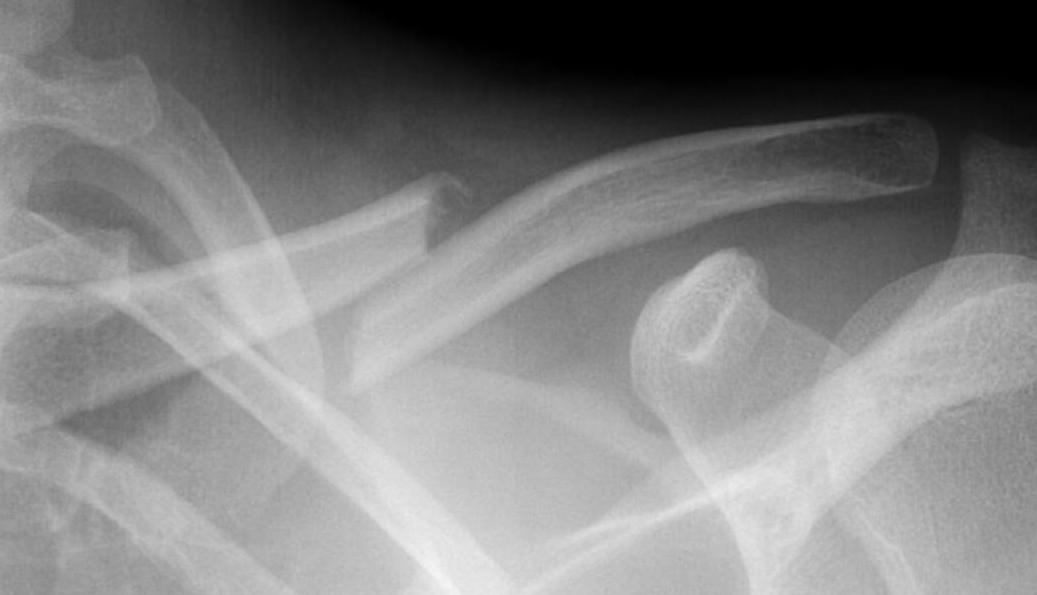

Shorted / displaced midshaft clavicle fractures

Z shaped midshaft clavicle fracture

Shortening

Displacement

- the proximal fragment elevated by sternocleidomastoid

- lateral fragment sags down with weight of shoulder